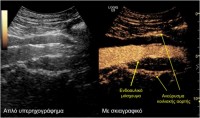

Σε αυτό το πλαίσιο εντάσσεται και ο μετεγχειρητικός υπερηχογραφικός έλεγχος που διεξήχθη στο Τμήμα Υπερήχων από τη Δρ. Κωνσταντίνα Κυριακοπούλου, MD, PhD, Διευθύντρια Τμήματος Υπερήχων, Ιατρικό Κέντρο Αθηνών και τον Ταξιάρχη Καράμπελα, MD, Ακτινολόγο, Αναπληρωτή Διευθυντή Τμήματος Υπερήχων, Ιατρικό Κέντρο Αθηνών. Το κέντρο αυτό ανήκει στα ελάχιστα ευρωπαϊκά κέντρα, τα οποία ελέγχουν τη βατότητα των σπλαγχνικών αγγείων και την επιτυχή ενδοαγγειακή αποκατάσταση των ανευρύσματων υπερηχογραφικά, με τη χρήση ειδικού σκιαγραφικού (SonoVue) που μεταβολίζεται αποκλειστικά στο ήπαρ. Αυτό αποτελεί ιδιαίτερο πλεονέκτημα σε ασθενείς με επηρεασμένη νεφρική λειτουργία.